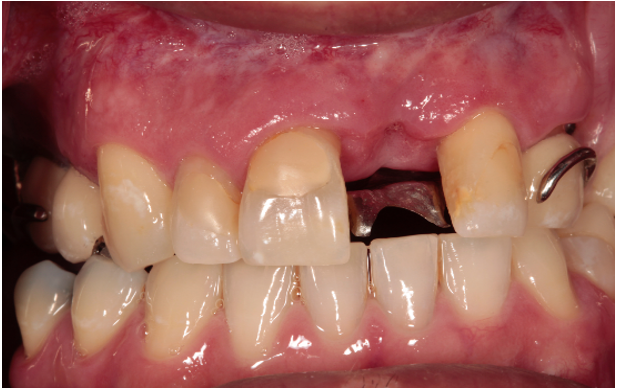

Due to the reflective properties of the metal base obturator, an alginate impression was made of the obturator in the patient’s mouth. After the impression set, the impression and the patient’s obturator were removed and poured in type IV dental stone while still combined After a retentive groove, palatal to site #9, was created in the RPD framework, the existing obturator and fabricated cast were coated with scanning spray (Scanspray, Renfert, USA) and scanned using an extraoral scanner (EOS) (inEos X5, Dentsply Sirona, USA). Digital scan of the opposing arch, and a buccal bite registration were also obtained using the same EOS. A custom abutment was designed in CAD software (Exocad), milled from wax, and cast in ticonium. Once the abutment was divested, it was seated into the retentive groove created in the framework and laser welded into place using an AlphaLaser ALP50 (Figs. 2 and 3).

Figure 3: Soldered maxillary central incisor abutment on obturator in the mouth.